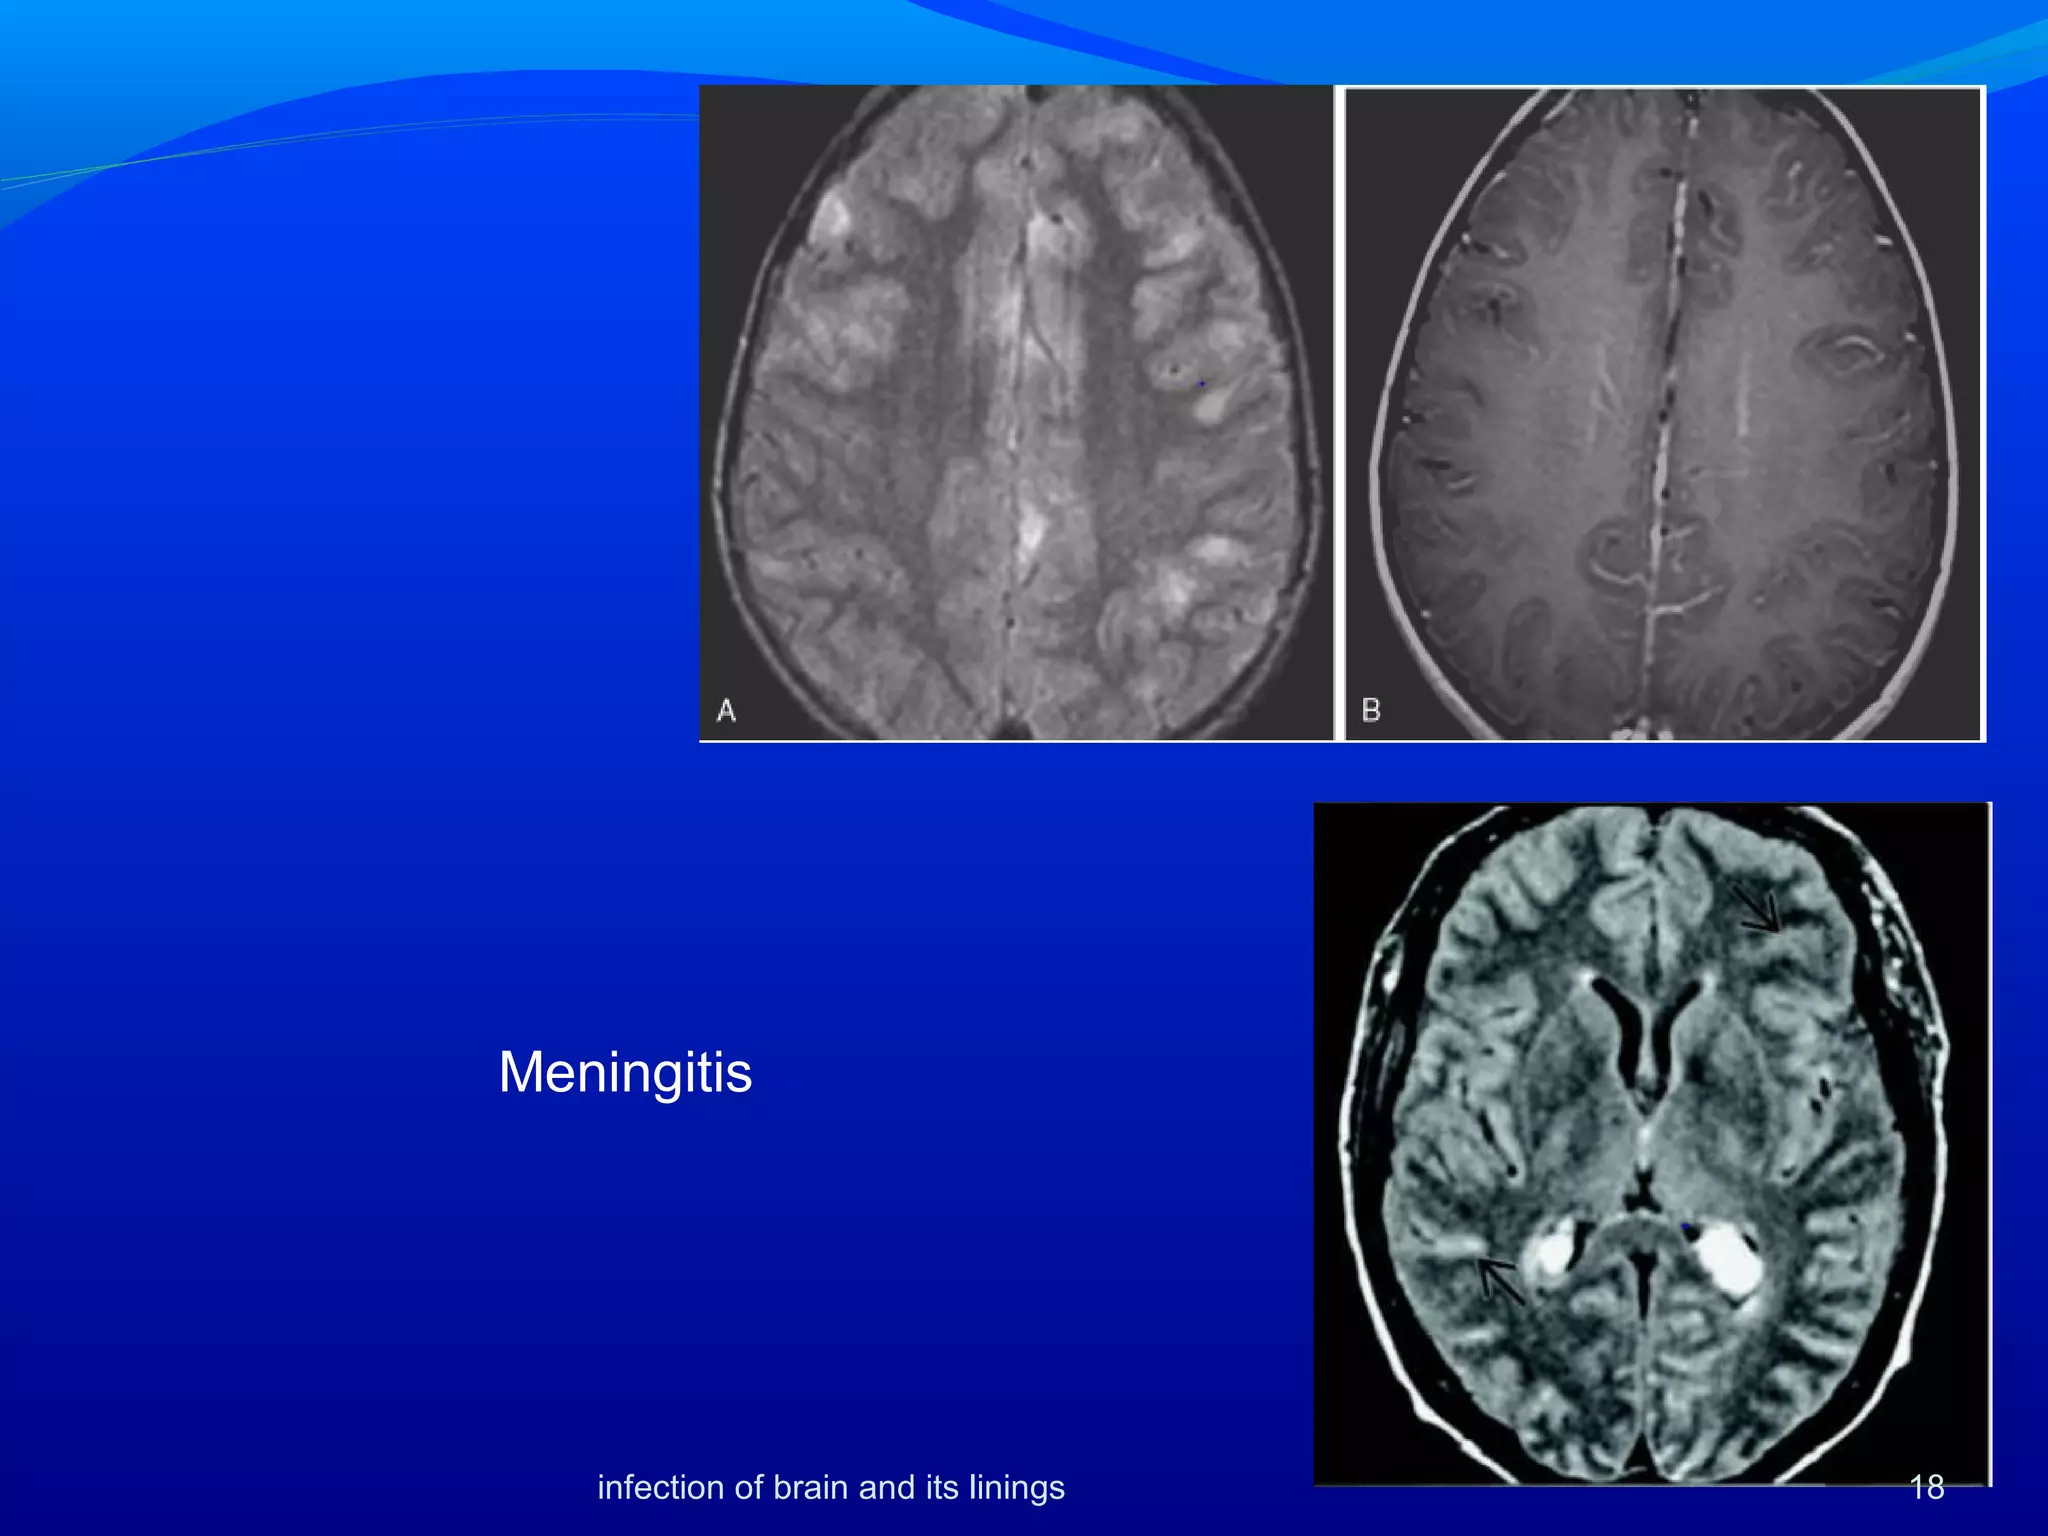

Imaging continue…

Routine MRI scans :obliteration of the basal cisterns on

T1-weighted images.

 Fluid-attenuated inversion recovery (FLAIR) sequence

may show hyperintensity of the cerebrospinal fluid (CSF)

within the subarachnoid space in contrast to the

hypointense CSF in the ventricles. Abnormal cortical

hyperintensity may be seen on T2-weighted images.

 Contrast-enhanced MRI studies may show basal cisternal

and sylvian enhancement as well as enhancement deep

within the cortical sulci

17infection of brain and its linings

Meningitis

18infection of brain and its linings